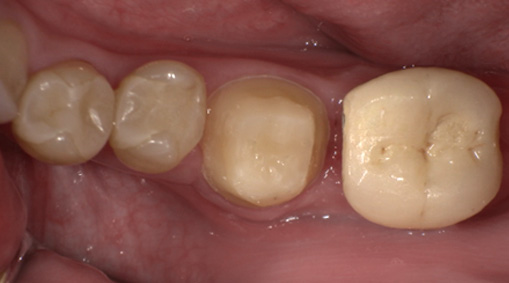

術前・術後の比較

| 術前 | 術後 |

9日目 最終的な被せ物をいれます。

自家歯牙移植の保険適用について

本症例は保険適用の条件を満たしていたため保険適用で治療いたしました。保険適用外の自家歯牙移植については1歯につき110,000円(税込)の費用となります。